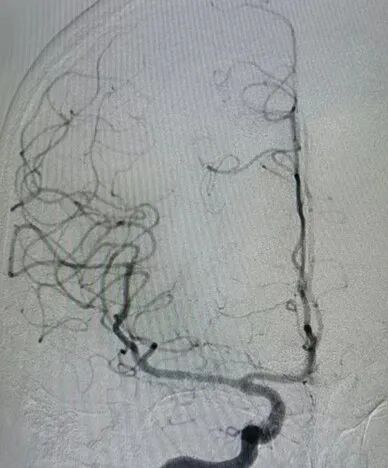

治疗中影像

Guiding到位,导丝通过病变。

导丝怎么扩【载药时代 球扩天下】NOVA DES®颅内药物洗脱支架在大脑中动脉重度狭窄的应用二例!_https://www.jmylbn.com_新闻资讯_第24张

球囊通过病变。

导丝怎么扩【载药时代 球扩天下】NOVA DES®颅内药物洗脱支架在大脑中动脉重度狭窄的应用二例!_https://www.jmylbn.com_新闻资讯_第25张

球囊扩张过程。

导丝怎么扩【载药时代 球扩天下】NOVA DES®颅内药物洗脱支架在大脑中动脉重度狭窄的应用二例!_https://www.jmylbn.com_新闻资讯_第26张

扩张后造影。

导丝怎么扩【载药时代 球扩天下】NOVA DES®颅内药物洗脱支架在大脑中动脉重度狭窄的应用二例!_https://www.jmylbn.com_新闻资讯_第27张

支架通过病变。

导丝怎么扩【载药时代 球扩天下】NOVA DES®颅内药物洗脱支架在大脑中动脉重度狭窄的应用二例!_https://www.jmylbn.com_新闻资讯_第28张

支架释放。

导丝怎么扩【载药时代 球扩天下】NOVA DES®颅内药物洗脱支架在大脑中动脉重度狭窄的应用二例!_https://www.jmylbn.com_新闻资讯_第29张